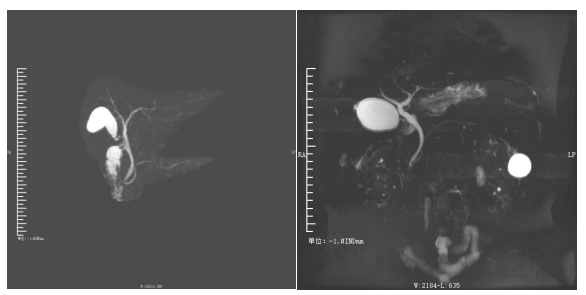

磁共振胰胆管水成像(MRCP)

胆总管结石(MRCP)